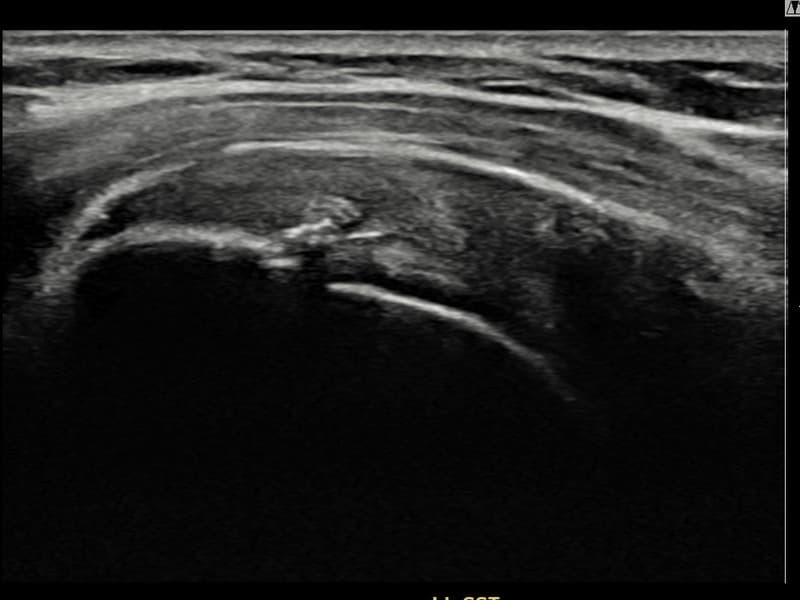

施術前

術前超音波にて左 棘上筋腱 関節面側部分断裂・左肩棘上筋腱のエコー不連続と腱欠損(8mm × 3mm (腱厚の約30%欠損))を確認。術後超音波では断裂部位が再生組織で充填され、腱の連続性回復とエコーパターンの正常化が確認されました。